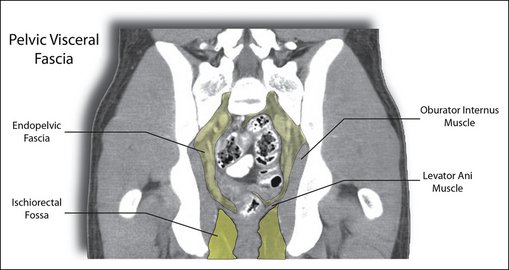

Plate 1.8.4 • A coronal plane reformatted CT image of the male pelvis. The endopelvic fascia is seen surrounding the visceral organs in the center of the pelvic basin. The levator ani separates the endopelvic fascia from the pannicular fascia located in the ischiorectal fossa. Courtesy of the Willard/Carreiro Collection.